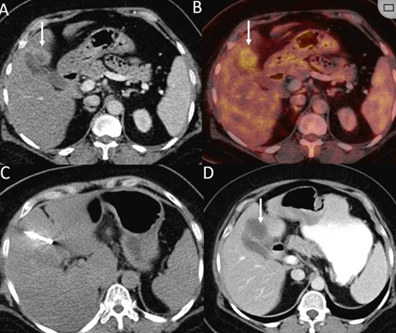

(A)動(dòng)脈期CT圖像顯示有一個(gè)包膜下結(jié)節(jié)(箭頭)。(B)門靜脈期CT圖像顯示病灶區(qū)(箭頭)。(C) 在手術(shù)過程中的CT顯示一個(gè)冷凍探針位于病灶內(nèi)。(D)消融后,術(shù)后1個(gè)月影像CT顯示完全消融。患者在手術(shù)及住院期間無并發(fā)癥及重大并發(fā)癥發(fā)生。隨訪時(shí)間中位數(shù)為7個(gè)月(范圍:3-12個(gè)月),隨訪期間患者無局部腫瘤進(jìn)展或死亡。

技術(shù)成功率為100%,本研究中77.8%(7/9)的患者達(dá)到了完全消融,輔助局部治療后,所有患者均完全消融。

膽囊附近轉(zhuǎn)移灶(來自子宮頸癌)的冷凍消融術(shù)(A)門靜脈期 CT 圖像顯示膽囊附近有病變(箭頭)。(C) 手術(shù)過程中CT 顯示冷凍探針位于病灶內(nèi)。(D)消融手術(shù)后 1 個(gè)月CT 顯示完全消融。

本研究中患者隨訪期間無局部腫瘤進(jìn)展,無死亡病例,沒有發(fā)現(xiàn)與手術(shù)相關(guān)的并發(fā)癥。證實(shí)冷凍消融是一種有效的治療方式,在技術(shù)上是可行和安全的。由于肝包膜下病變位置特殊,射頻消融有出血及腫瘤種植的風(fēng)險(xiǎn),可能會(huì)對(duì)鄰近器官造成損傷,并且增加局部腫瘤進(jìn)展的風(fēng)險(xiǎn)。近年來,冷凍消融術(shù)的應(yīng)用逐漸廣泛,有研究顯示冷凍消融治療具有明顯優(yōu)勢(shì),可治療特殊部位的肝腫瘤。本研究的目的是評(píng)價(jià)冷凍消融治療肝包膜下腫瘤的安全性和有效性。回顧性納入2016年7月1日至2018年9月1日期間冷凍消融的57例患者。包括42例男性和15例女性,平均年齡為62.4歲(范圍:48-82歲)。每個(gè)患者有1個(gè)或2個(gè)平均腫瘤尺寸為2.4cm的病變(范圍:0.6-4.0cm)。所有患者均患有慢性肝病或肝硬化,并伴有乙型肝炎(n=52)、丙型肝炎(n=3)和其他肝炎(n=2)。根據(jù)腫瘤位置,在膈肌或肝臟下附近有18個(gè)病變(26.5%),胃或腸附近有9個(gè)病變(13.2%),腹壁附近有33個(gè)病變(48.5%),腎臟附近有8個(gè)病變(11.8%)。